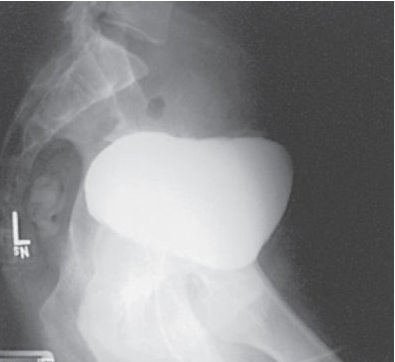

What is this projection?

Left lateral